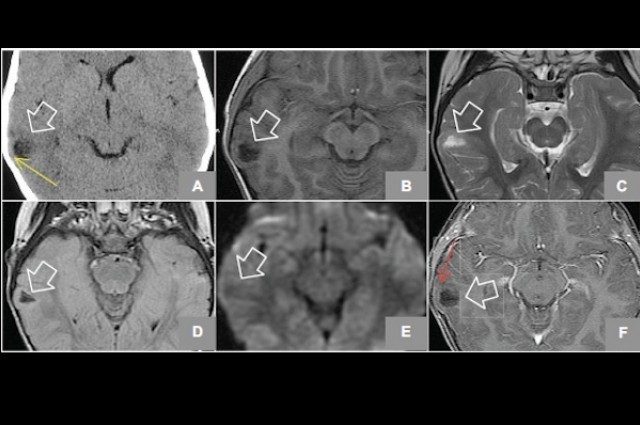

După ce părinţii au dus-o la spital ca să afle ce se întâmplă, medicul Jose Liders Burgos şi colegii săi i-au făcut o tomografie.

Astfel, ei au descoperit că fata avea pe creier un hamartom, o formaţiune pseudotumorală mică, benignă, care apăsa pe lobul temporal, provocând aceste crize.